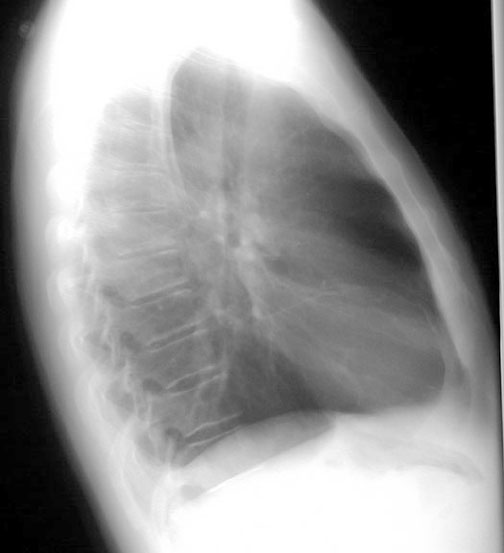

Spine

Labeled Image What are the pulmonary manifestations of Ankylosing spondylitis?